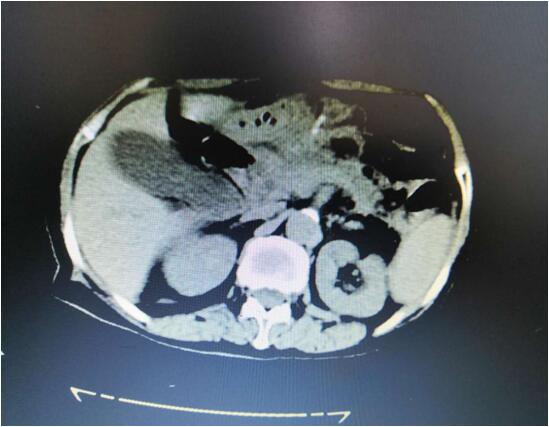

患者A,女,72歲,1年前因急性出血壞死性胰腺炎,曾行腹腔鏡下壞死胰腺組織清創(chuàng)+外引流術(shù),術(shù)后出現(xiàn)急性胰腺假性囊腫,囊腫越來越增大,以至于病人不能做下蹲和彎腰動作,給生活造成極大不便。本次患者因急性腹痛入院,入院診斷為:胰腺巨大假性囊腫并發(fā)出血,重癥胰腺炎清創(chuàng)術(shù)后。

(術(shù)前腹部CT顯示胰腺巨大假性囊腫)